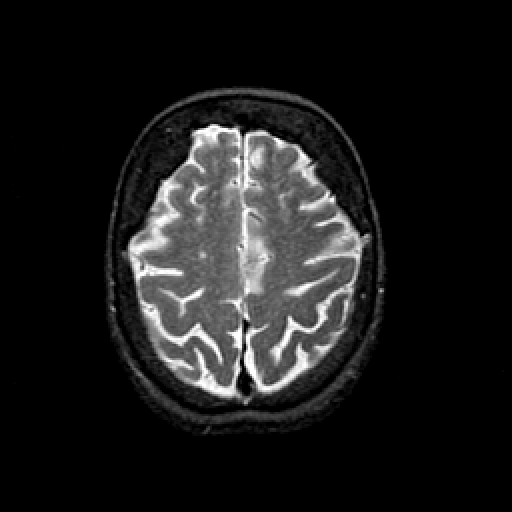

T2-weighted structural MR: Slice 41

Slice 41